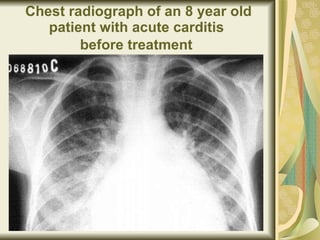

Chest radiograph of an 8 year old patient with acute carditis  before treatment

Same patient after 4 weeks